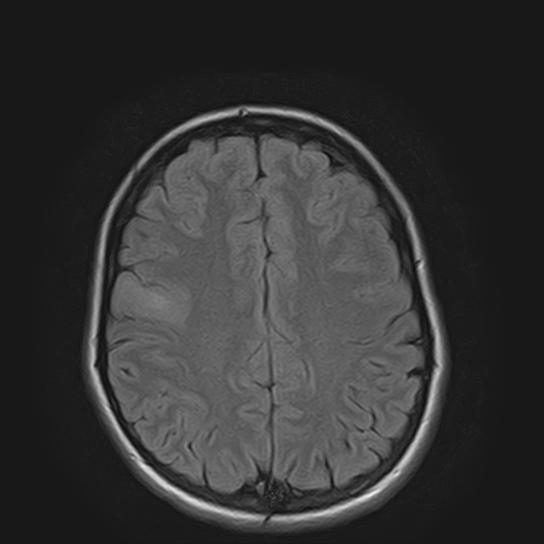

«Например, недавно в отделение поступил подросток с постепенно нарастающей очаговой неврологической симптоматикой. По результатам МРТ головного мозга была выявлена опухоль в функциональнозначимой зоне головного мозга (отвечающей за движение в конечностях) и без отчетливых границ с мозговой тканью. Открытое удаление новообразования могло привести к инвалидизации девочки, однако для определения дальнейшей тактики лечения требовался гистологический анализ патологической ткани с целью исключения злокачественного характера бластоматозного процесса. Было решено провести стереотаксическую биопсию с использованием нейронавигационной станции. Для проведения предварительных расчетов безопасной траектории прохождения биопсионной иглы до зоны-мишени (центральной части опухоли) в навигационную станцию были загружены данные МРТ обследования пациентки, затем в режиме реального времени были привязаны внешние анатомические ориентиры головы и лица. После компьютерной обработки полученных данных весь ход операции можно было контролировать на мониторе навигационной станции в трехмерном режиме. При помощи специальной биопсийной иглы были взяты образцы патологической ткани в намеченной зоне (что было подтверждено при контрольной МРТ)», — рассказывает заведующий отделением нейрохирургии для детей №7 к.м.н. Александр Вонгиевич Ким.

Визуализация введения иглы во время стереотаксической биопсии

Пациентка перенесла операцию удовлетворительно, осложнений в постоперационном периоде не было. Гистологический анализ подтвердил наличие опухоли, она оказалась доброкачественной, поэтому девочке не было показано онкостатическое лечение. Было лишь рекомендовано проходить регулярный МРТ контроль.

| МРТ до операции | МРТ после операции (1-е сутки после операции) | |